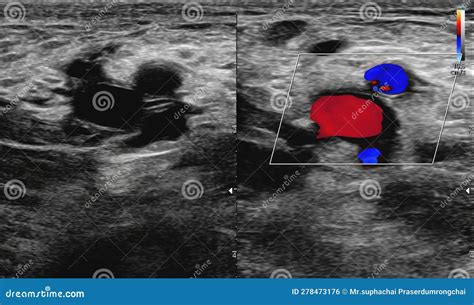

One such advancement is the use of Doppler ultrasound, which not only provides visual images but also measures the speed and direction of blood flow. This information can help healthcare providers assess the severity of blockages more accurately.

Carotid Artery Ultrasound